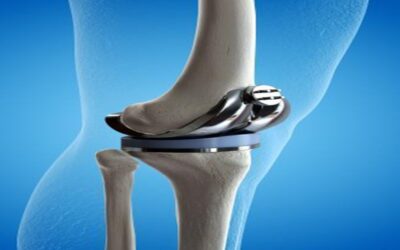

হাঁটু ও জয়েন্ট সমস্যা

নি-রিপ্লেসমেন্ট (Knee Replacement): হাঁটুর ব্যথা থেকে মুক্তির আধুনিক চিকিৎসা

নি-রিপ্লেসমেন্ট (Knee Replacement): হাঁটুর ব্যথা থেকে মুক্তির আধুনিক চিকিৎসা মূল কথা: বয়স বাড়ার সাথে সাথে হাঁটুর হাড়ের…